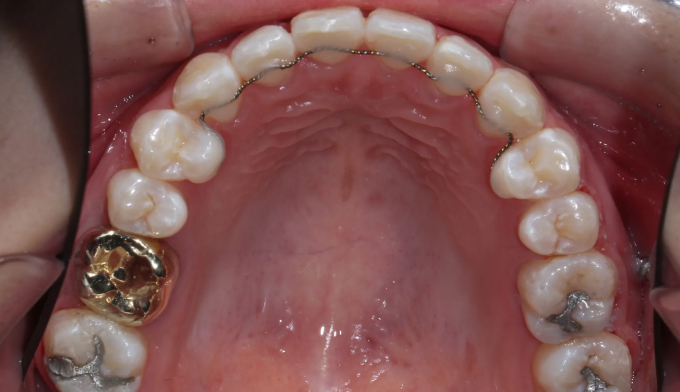

미니스크류를 이용하여 어금니 교합을 변화시켜 개방교합을 해소하였습니다. 이와 동시에 어금니의 후상방 이동으로 앞니 배열공간을 만들었고 앞니를 가지런하게 배열시킬 수 있었습니다.

치아교정이 진행되면서 구강위생관리가 좋지않아 잇몸 염증과 초기 충치가 다수 관찰되었습니다.

교정치료 중에는 보다 더 철저히 구강위생관리에 신경을 써야 합니다.